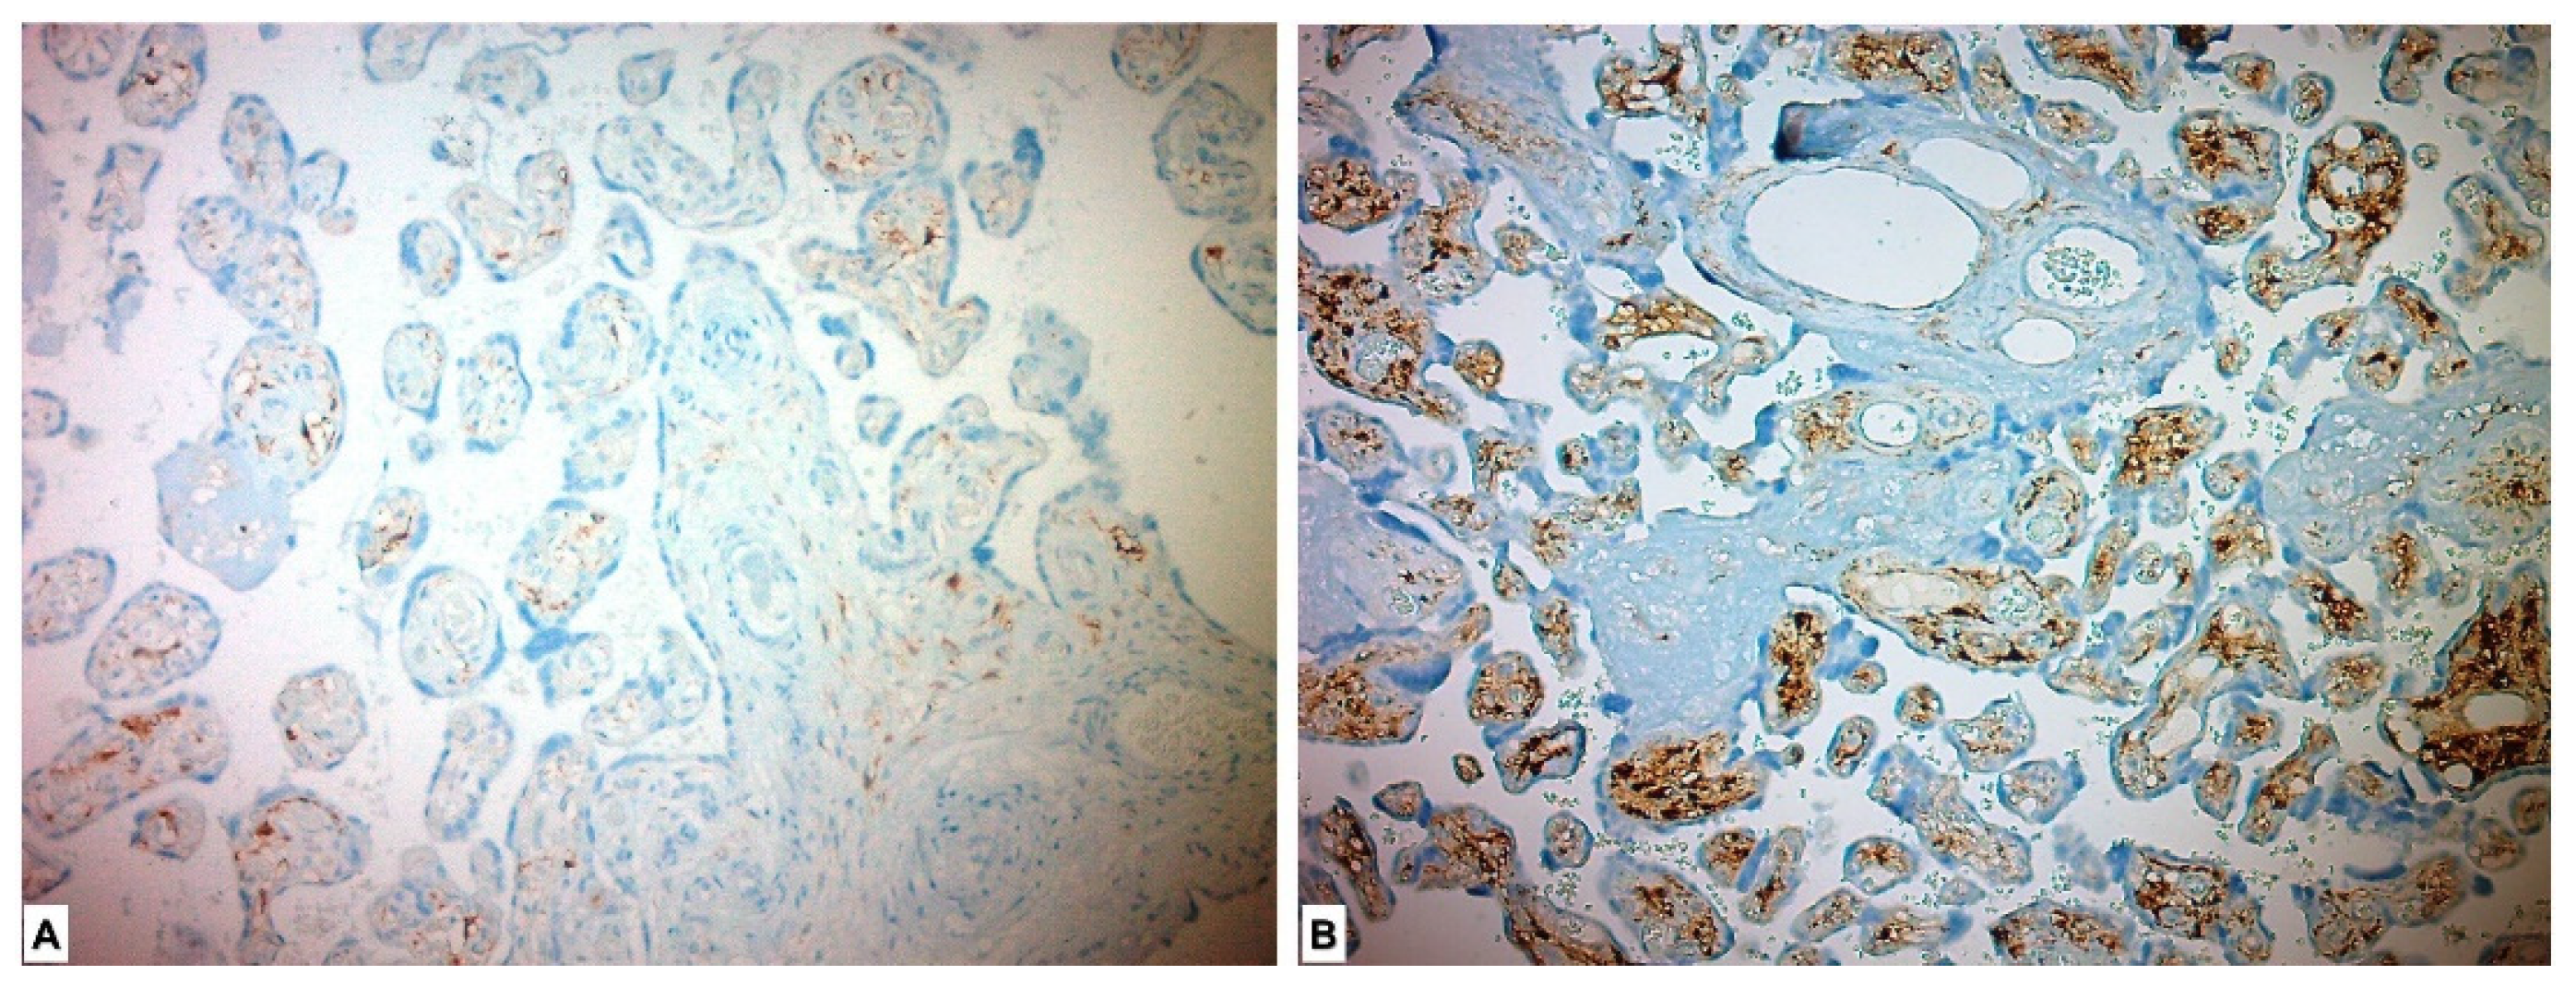

In the immunohistochemical study for the ADAM17 Ab, it was expressed as high in all the placentas of the study group patients and low in all the placentas in the control group. ADAM17 Ab stained more in the placentas in the study group, and a significant difference was detected between the two groups (p < 0.001) (Table 3, Figure 3).

Figure 3.

Immunohistochemical ADAM17 expression in placental tissues. (A) Low ADAM17 expression in control group placenta. (B) High ADAM17 expression in chorionic villous stromal cells, syncytiotrophoblasts and cytotrophoblasts in preeclamptic placenta.

In the immunohistochemical study performed for the FGF21 Ab, it was expressed as low in 1 (1.8%) placenta in the study group and highly expressed in 55 (98.2%) placentas. FGF21 showed low expression in all placentas in the control group. A statistically significant difference was found between the two groups (p < 0.001) (Figure 4, Table 3).

Figure 4.

Immunohistochemical FGF21 expression in placental tissues. (A) Low FGF21 expression in chorionic villous stromal cells in the control group placenta. (B) High FGF21 expression, which is more pronounced in chorionic villous stromal cells of preeclamptic placental tissues.